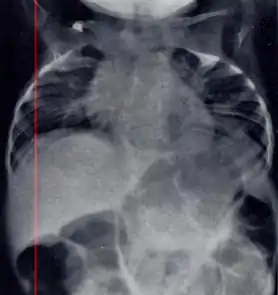

| Radiograph depicting typical skeletal features of Jarcho-Levin syndrome, subtype spondylothoracic dysplasia. Note fanlike configuration of the ribs, with extensive posterior fusion, along with multiple vertebral segmentation defects. | |

In contrast to STD, the subtype spondylocostal dysostosis, or SCD features intrinsic rib anomalies, in addition to vertebral anomalies. Intrinsic rib anomalies include defects such as bifurcation, broadening and fusion that are not directly related to the vertebral anomalies (such as in STD, where extensive posterior rib fusion occurs due to segmentation defects and extreme shortening of the thoracic vertebral column).[6] In both subtypes, the pulmonary restriction may result in pulmonary hypertension, and have other potential cardiac implications.[7]